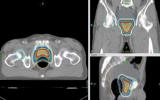

[제주건강보고서] [제주, 제주인의 건강보고서 Ⅷ 건강다이어리] (137)전립선암

전립선암 남성 암 유병·사망률 최상위권인 대표적 악성 질환수술 대신 방사선 치료 활용… 장기 전이 시 증상 완화 효과 [한라일보] 전립선 암은 미국, 유럽 등지에서 전체 남성 암 중 유병률 및…